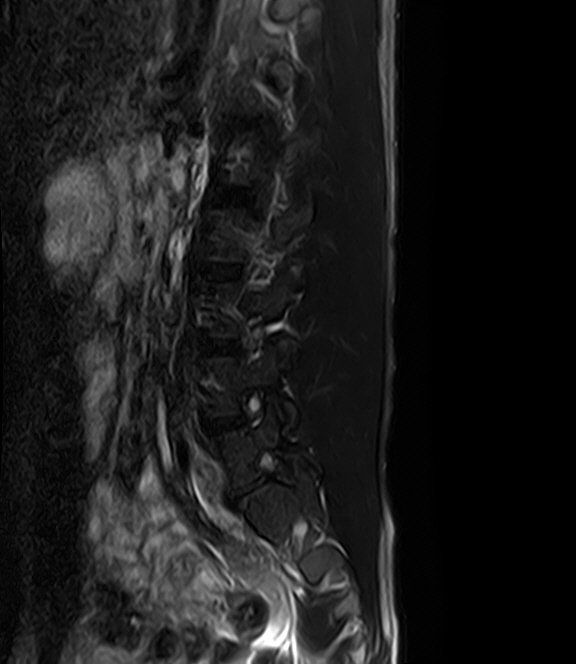

선생님 요추 Mri 판독부탁드립니다 ㅠㅠ

예전 진료에서 척추전방전위증과 그로인한 퇴행성 디스크 그리고 팽윤이 있다고 들었습니다.

현재 제가 디스크가 터진곳이 있을까요?

집근처 병원을 세곳을다니는중인데 어떤곳은 디스크는 멀쩡하다 퇴행성만있을뿐.

어떤곳은 디스크가 터졌다고 하는게 어떤곳이 맞는건가요?

혹시 디스크가 터진게 없다면 통증이 생기는이유는 단순히 척추전방증으로인한 퇴행성디스크와 팽윤 때문인건가요?

디스크가 명확하게 튀어나와 신경뿌리를 압박하는 병변은 보이지 않는 MRI로 생각됩니다.